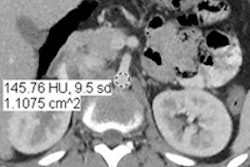

In this scientific session, Duke University researchers will present their software algorithm for automatically segmenting organs in contrast-enhanced abdominal CT scans.Delineation of organs on CT scans is a key component to computer-aided detection, radiotherapy planning, and presurgical planning. However, manual segmentation is often labor-intensive and suffers from intraobserver and interobserver variation, said researcher Qiang Li, PhD.

Automatic and semiautomatic segmentation methods have been proposed, but they remain challenging in comprehensive clinical studies, Li said. As a result, the researchers sought to develop a generic algorithm for segmentation of multiple abdominal organs from contrast-enhanced CT scans.

The team's automated segmentation algorithm was found to greatly improve the efficiency and consistency of organ localization and contouring, according to Li.

"It facilitates computer-aided detection, radiotherapy, and presurgical planning in clinical practice," Li told AuntMinnie.com.